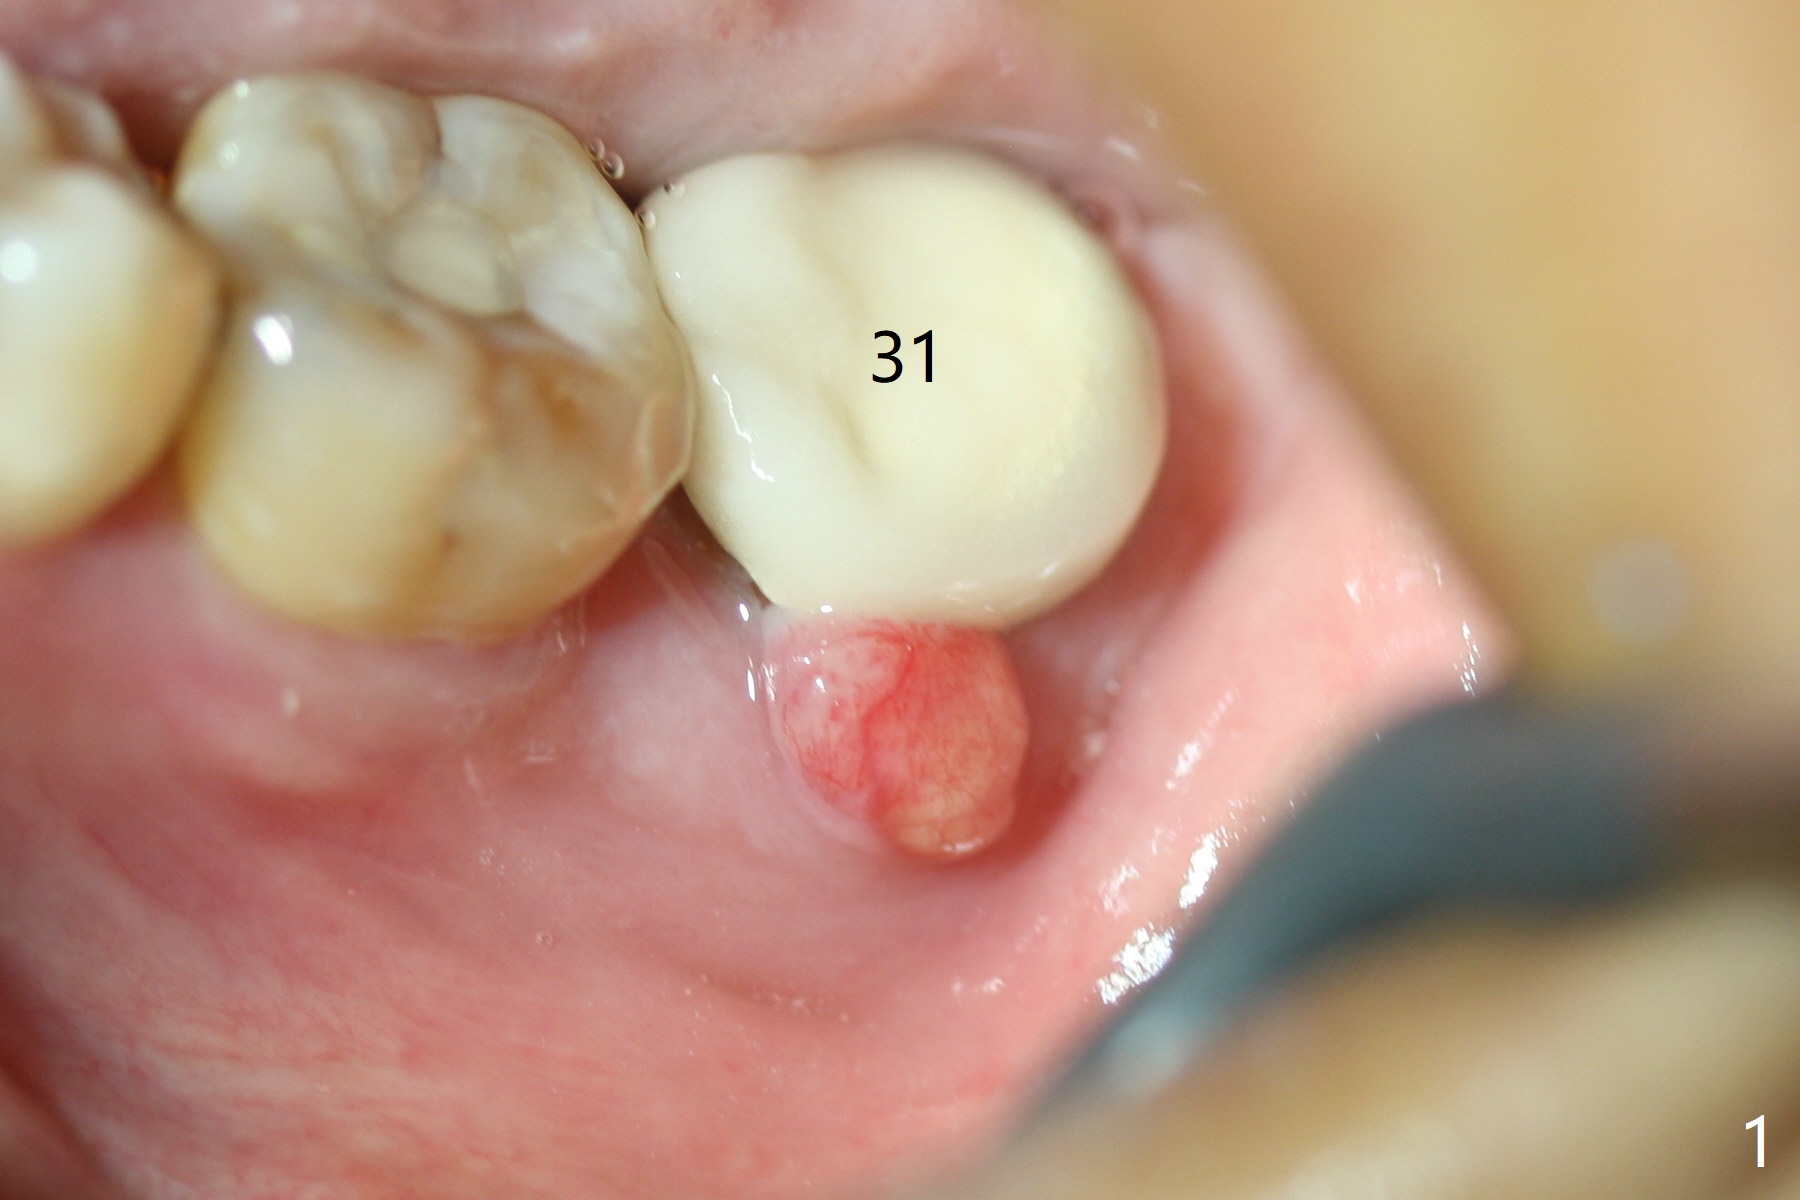

If the patient were not nervous and every step were followed by X-ray, light osteotomy in the bottom of the socket (flattening) may increase primary stability. A larger implant (9 or 10 mm) is a solution. The socket heals with disappearance of the fistula 2 weeks postop (Fig.5,6), but the ridge seems to have been reduced in width. The patient return for follow up 4 months postop; bone graft appears to remain in the socket (Fig.7). The ridge is apparently reduced further (data not shown). The patient prefers to have implant placement 1 month later. Take photos of the ridge buccally when the patient returns. In fact the patient agrees to have guided surgery. She postpones the surgery due to sickness for one more month. Implant placement will occur 6 months post extraction. The bone density should be higher than earlier.